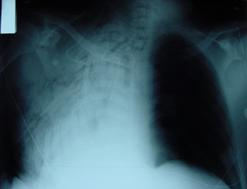

Contuzie pulmonara stanga Contuzie pulmonara dreapta

Contuzie pulmonara dreapta.Imagine CT